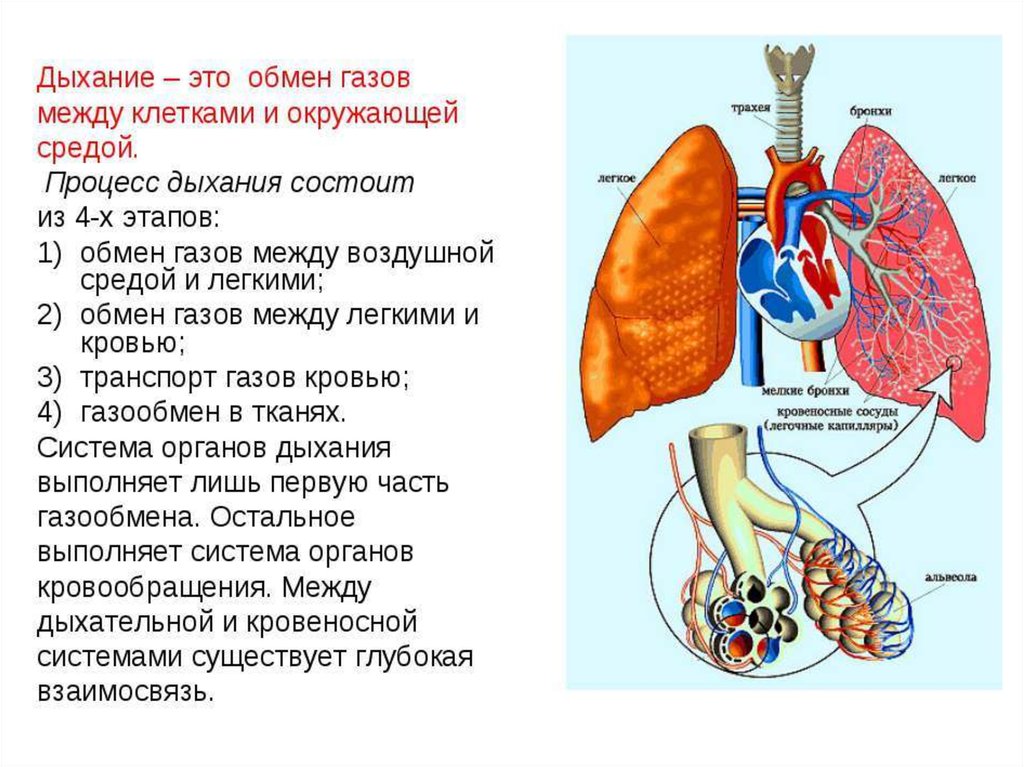

Роль легких в метаболических процессах

Раздел: Альбом идей